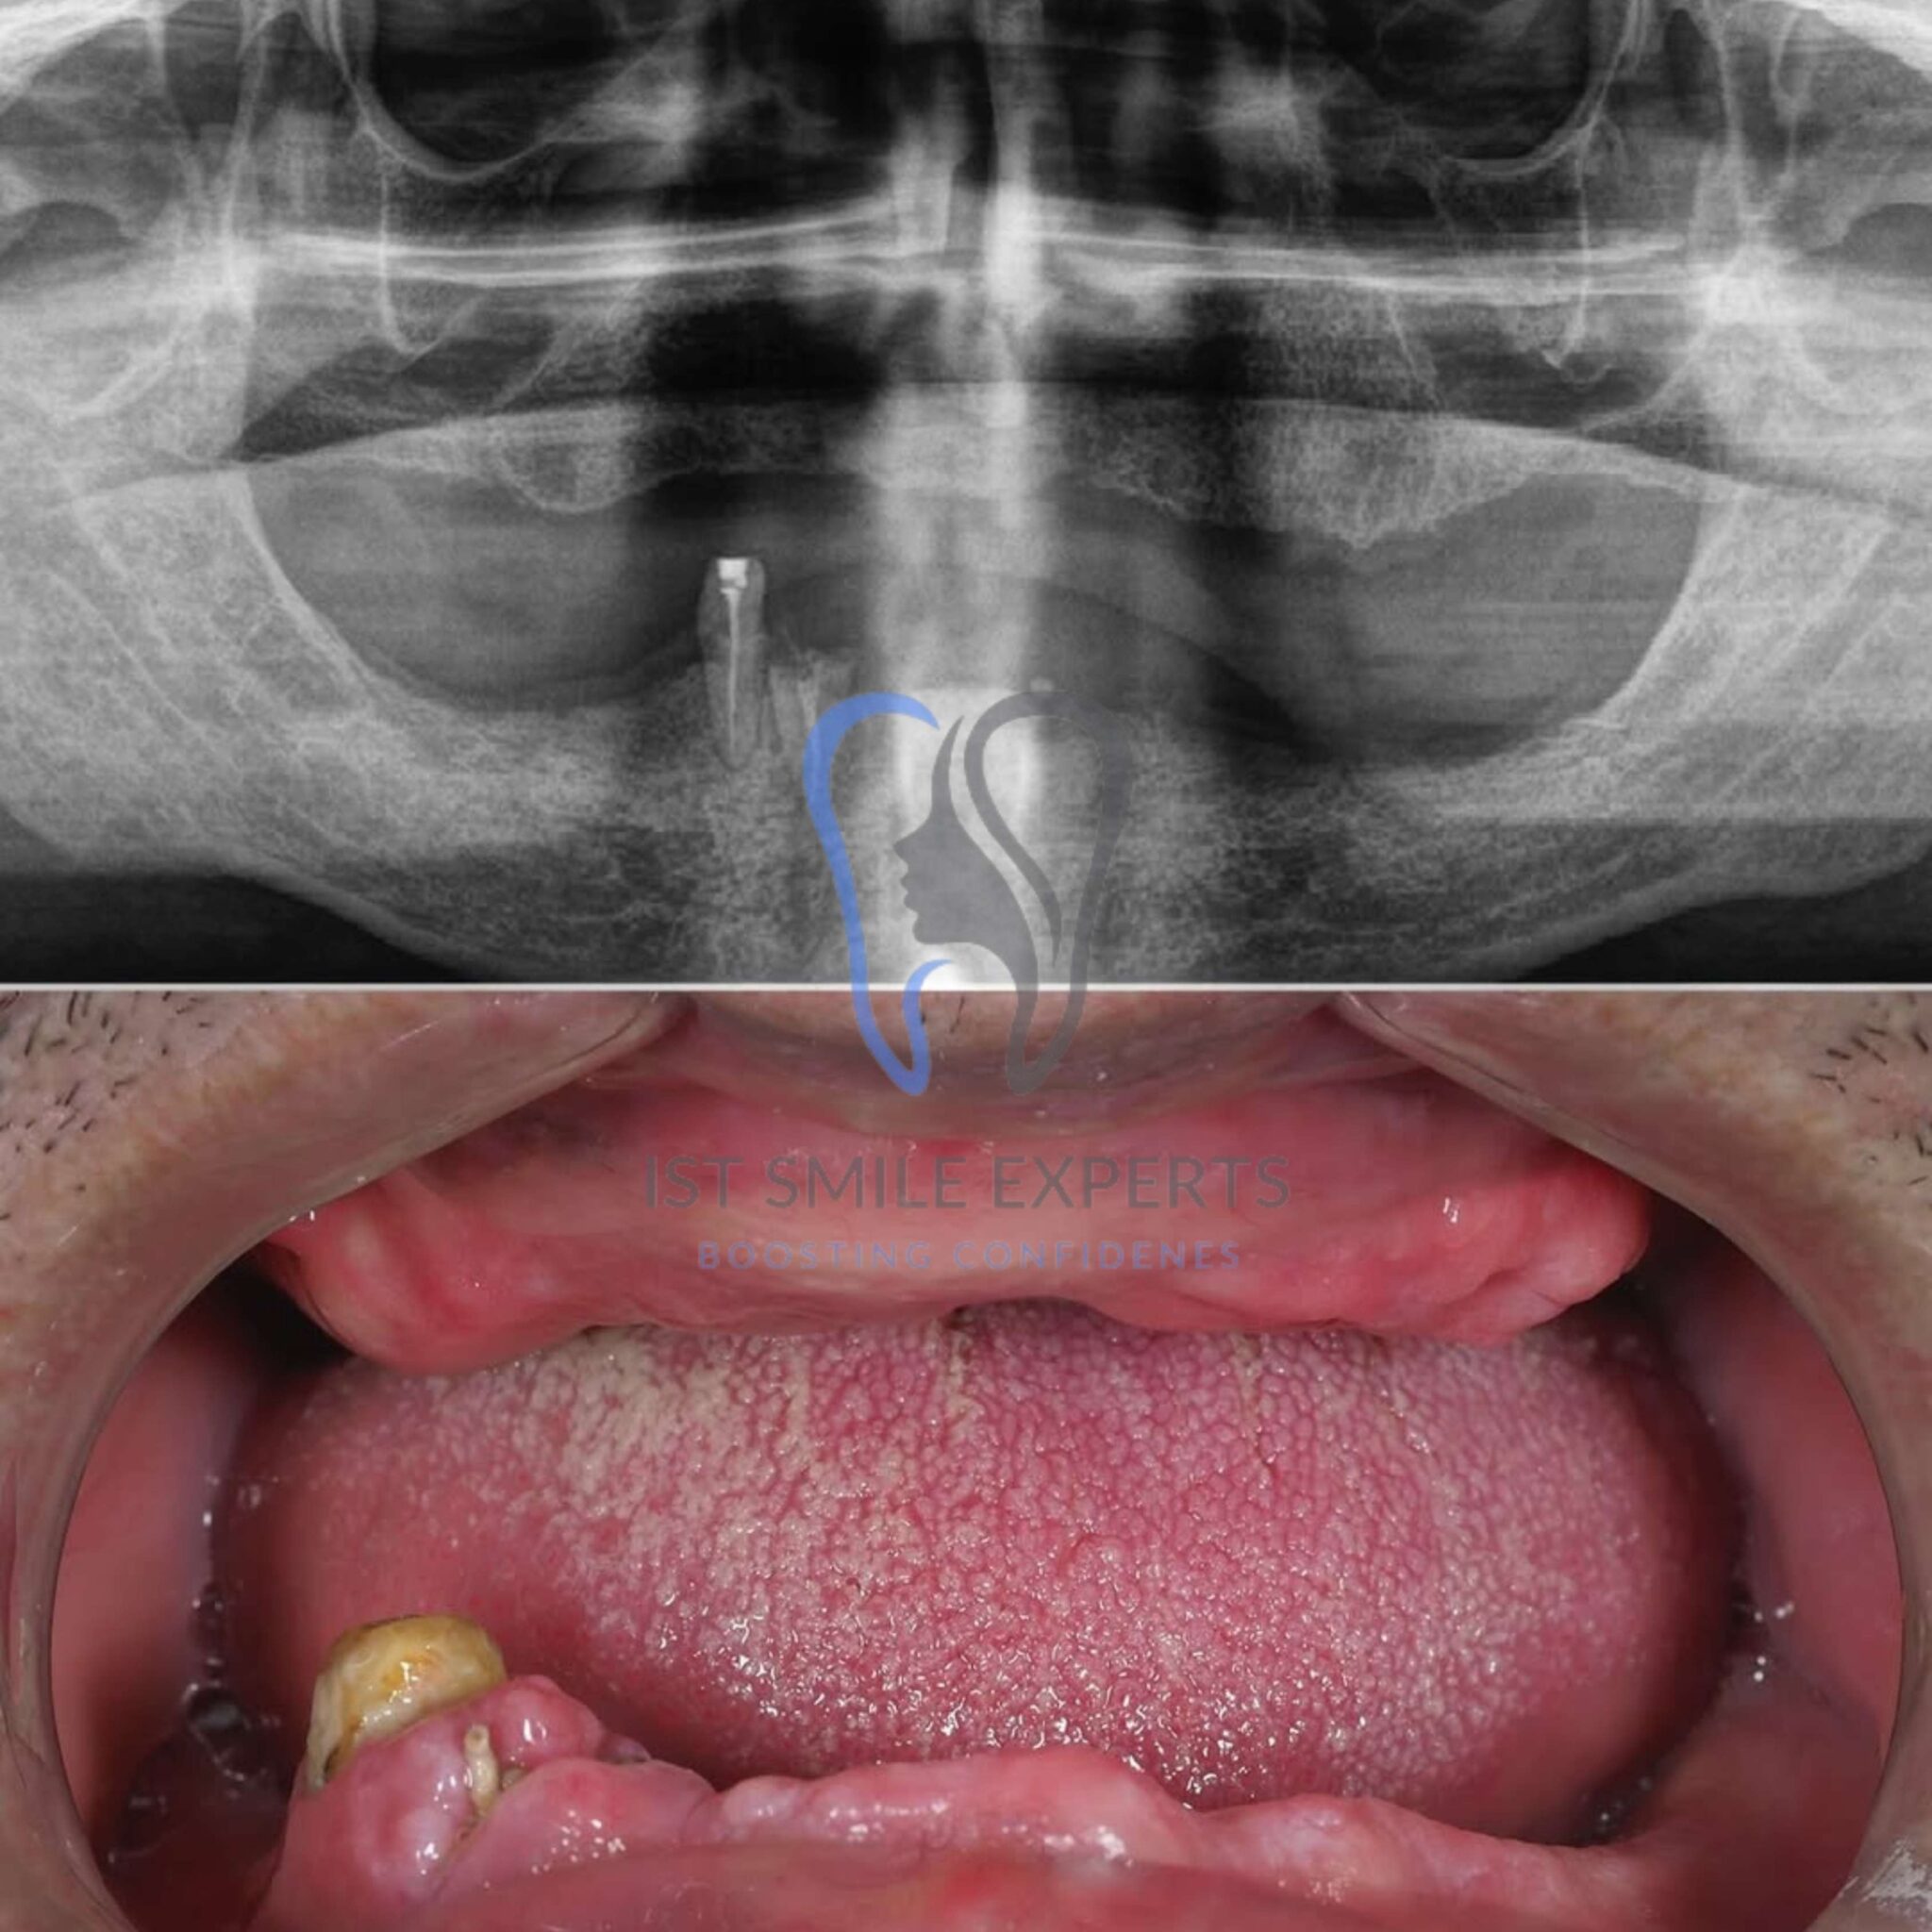

We begin your journey with a detailed assessment. Our team utilizes advanced 3D imaging to evaluate your bone structure. Furthermore, this allows us to create a precise, personalized treatment plan.

Phase 2: Implant Placement Surgery

This surgical phase involves placing premium German or Swiss dental implants into your jawbone. Our surgeons perform this procedure under local anaesthesia. Moreover, we often attach a temporary set of teeth immediately after, allowing you to leave with a functional smile on the same day.

Phase 3: Healing & Osseointegration

After implant placement, a healing period of 3-6 months is necessary. During this time, the implants integrate with your jawbone. Essentially, the bone fuses with the implant, creating a strong foundation. Following post-operative care instructions is vital during this period.